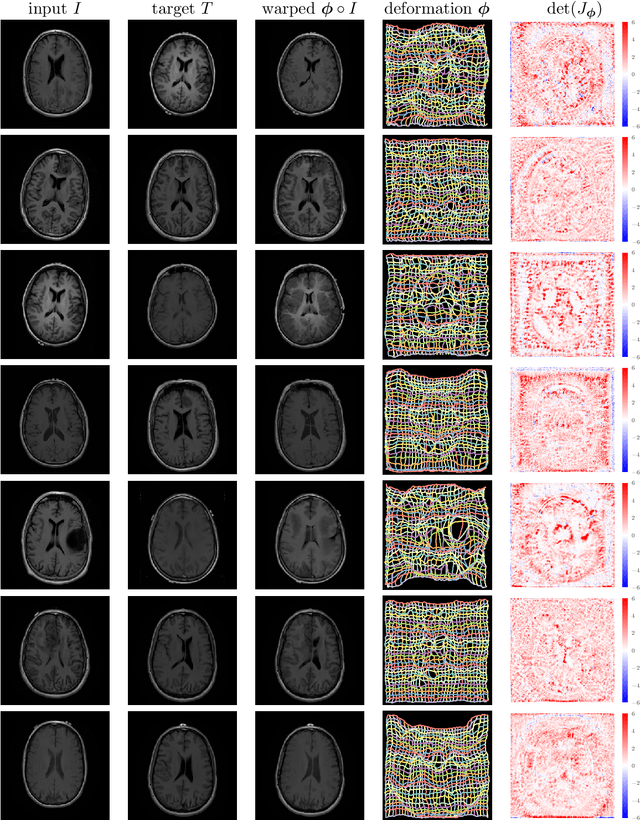

Abstract:We present deformable unsupervised medical image registration using a randomly-initialized deep convolutional neural network (CNN) as regularization prior. Conventional registration methods predict a transformation by minimizing dissimilarities between an image pair. The minimization is usually regularized with manually engineered priors, which limits the potential of the registration. By learning transformation priors from a large dataset, CNNs have achieved great success in deformable registration. However, learned methods are restricted to domain-specific data and the required amounts of medical data are difficult to obtain. Our approach uses the idea of deep image priors to combine convolutional networks with conventional registration methods based on manually engineered priors. The proposed method is applied to brain MRI scans. We show that our approach registers image pairs with state-of-the-art accuracy by providing dense, pixel-wise correspondence maps. It does not rely on prior training and is therefore not limited to a specific image domain.